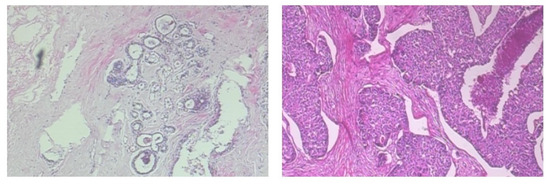

4.1. Dataset Description

| Tissue | Magnifications | Number of Images |

|---|---|---|

| adrenal | , | 50 |

| gland | , | 50 |

| breast | , | 40 |

| colon | , , | 60 |

| prostate | , | 70 |

| Type | Magnifications | Number of Images |

| benign tumor | , , , | 2480 |

| malignant tumor | , , , | 5429 |